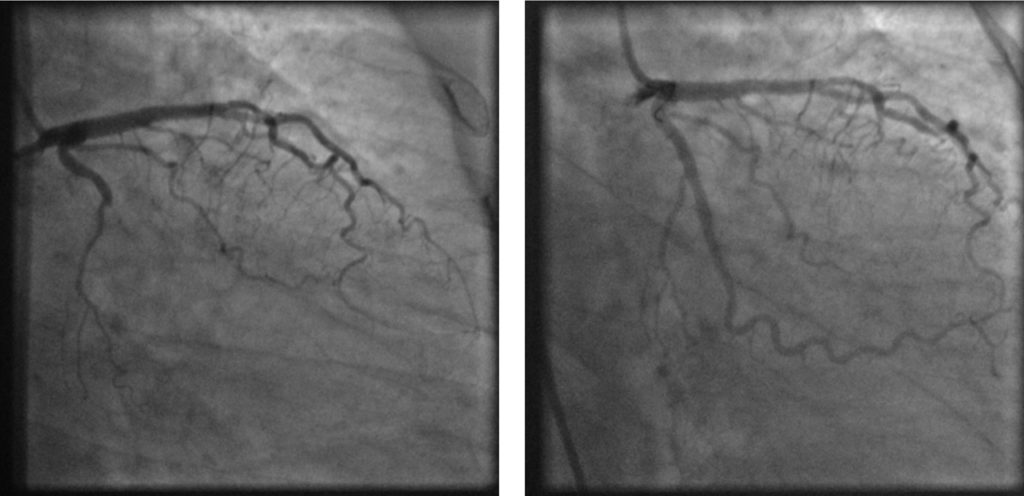

Interventional Cardiology – Submit your best Coronary or Structural Heart case. The four best will be selected for presentation on Saturday June 21, 2025 during the Cors/Vasc at the Shore Interventional Cardiology Session.

• Utilize high quality images and video visually displaying complication, solution and result